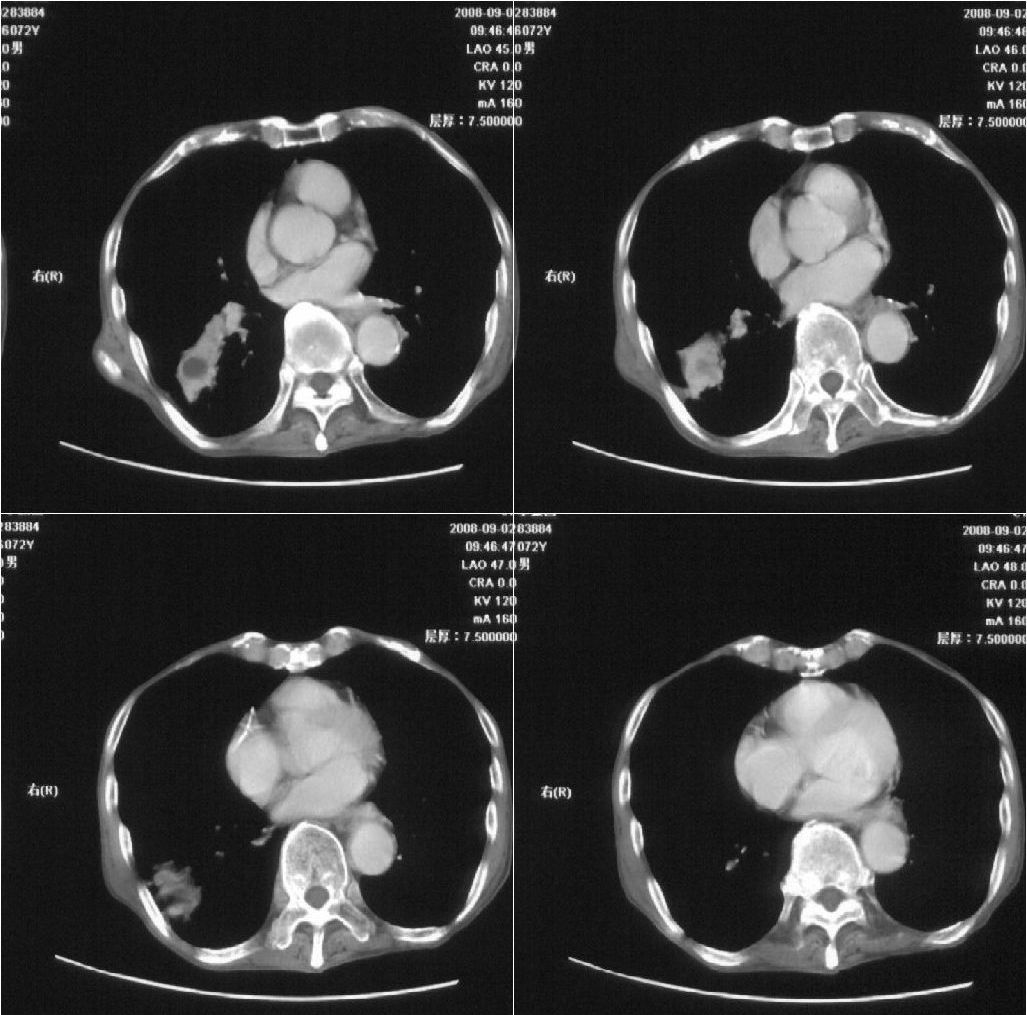

标题: CT15789:男性,72岁。食管癌术后14年。 [打印本页]

标题: CT15789:男性,72岁。食管癌术后14年。

痰培养:见葡萄球菌,霉菌少量生长。(此片系外院所作,仅提供了增强后的ct值为100hu,中心的坏死部分无强化,患者现在身体状况欠佳,为恶液质状态)

考虑肺癌可能性大伴阻塞性炎症

注意排外食管支气管瘘引起的肺部感染

周围型肺癌可能性大.

考虑右肺下叶感染性病变(肺脓肿?);建议抗炎治疗后复查。

病人无发热,消瘦,考虑ca

考虑右下肺慢性感染性病变

符合机遇性感染,真菌可能性大。